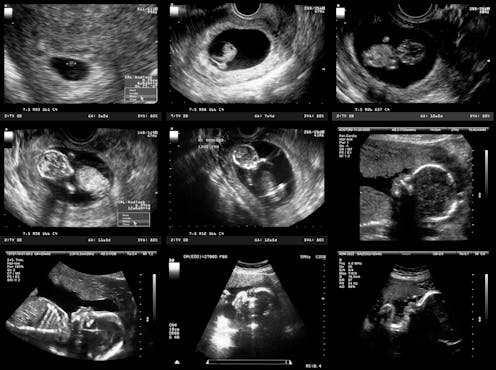

Scott Gilbert, the Howard A. Schneiderman Professor of Biology emeritus at Swarthmore College, is the author of the standard textbook of developmental biology. He has identified as many as five developmental stages that, from a biological perspective, are all plausible beginning points for human life. Biology, as science knows it now, can tell these stages apart, but cannot determine at which one of these stages life begins.

The first of these stages is fertilization in the egg duct, when a zygote is formed with the full human genetic material. But almost every cell in everyone’s body contains that person’s complete DNA sequence. If genetic material alone makes a potential human being, then when we shed skin cells – as we do all the time – we are severing potential human beings.

The second plausible stage is called gastrulation, which happens about two weeks after fertilization. At that point, the embryo loses the ability to form identical twins – or triplets or more. The embryo therefore becomes a biological individual but not necessarily a human individual.

The third possible stage is at 24 to 27 weeks of pregnancy, when the characteristic human-specific brain-wave pattern emerges in the fetus’s brain. Disappearance of this pattern is part of the legal standard for human death; by symmetry, perhaps its appearance could be taken to mark the beginning of human life.

The fourth possible stage, which is the one endorsed in the Roe v. Wade decision legalizing abortion in the United States, is viability, when a fetus typically becomes viable outside the uterus with the help of available medical technology. With the technology that we have today, that stage is reached at about 24 weeks.

The final possibility is birth itself.